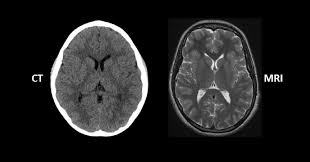

- CT(Computed Tomography): X선을 여러 각도에서 쏜 뒤 컴퓨터로 재구성해 단면 영상을 얻는 검사입니다. 쉽게 말해 고성능 X-ray를 360도에서 찍고 컴퓨터가 합쳐주는 방식입니다.

- MRI(Magnetic Resonance Imaging): 강력한 자기장과 전파를 이용해 인체의 수소 원자 반응을 영상화하는 방식입니다. 방사선을 사용하지 않고 자기장을 이용한다는 점이 CT와 큰 차이입니다.

- CT: 폐, 간, 신장, 뼈처럼 구조가 뚜렷하고 밀도 차이가 큰 장기를 잘 보여줍니다. 특히 교통사고 외상, 뇌출혈, 폐렴, 암 전이 확인 등에 널리 쓰입니다.

- MRI: 뇌, 척수, 근육, 인대, 연골처럼 연부조직(soft tissue)을 정밀하게 볼 수 있습니다. 뇌종양, 허리디스크, 무릎 인대 손상 같은 경우 MRI가 필수적입니다.

- CT 장점: 검사 속도가 빠르고, 응급실에서 바로 확인이 가능하며 비용이 저렴합니다. 단점은 방사선 피폭이 있다는 점입니다.

- MRI 장점: 방사선이 전혀 없고, 연부조직 표현력이 뛰어나 훨씬 정밀한 영상이 가능합니다. 단점은 검사 시간이 길고(30분~1시간), 소음이 크며, 비용이 비쌉니다.